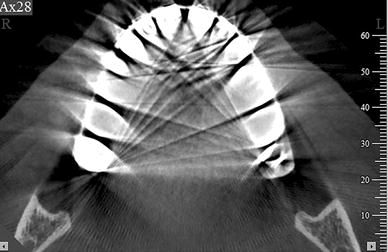

- CBCT imaging is performed using a rotating platform or gantry carrying an x-ray source and detector.

- A divergent cone-shaped or pyramidal source of radiation is directed through the region of interest (ROI), the residual attenuated radiation beam is projected onto an area x-ray detector on opposite side.

- The x-ray source and detector rotate around a rotation center, fixed within the center of ROL. This rotational center becomes the center of the final acquired image volume.

- During the rotation, multiples sequential planar projection images are obtained while the x-ray source and detector move through an arc of 180 to 360 deg.

- These single projection images constitute the raw primary data and are individually referred to as basis, frame or raw images.

- There are usually several hundred two-dimensional basis images from which the image volume is calculated and constructed.

- The complete series of images is referred to as the projection data. The softwares including algorithms are applied to these projection data to generate a volumetric data set that can be used to provide primary reconstruction images in three orthogonal planes (axial, sagittal and coronal).